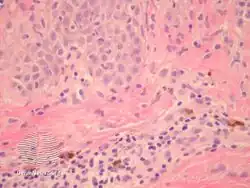

pathology-Prurigo pigmentosa